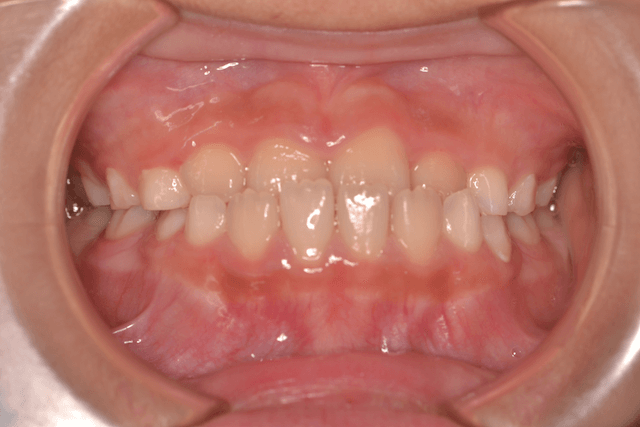

受け口(反対咬合・下顎前突)の症例

受け口(反対咬合・下顎前突)をリンガルアーチ、セクショナルDBSで改善した症例

10歳男性

前歯のかみ合わせ

リンガルアーチ、セクショナルDBS

3年5か月